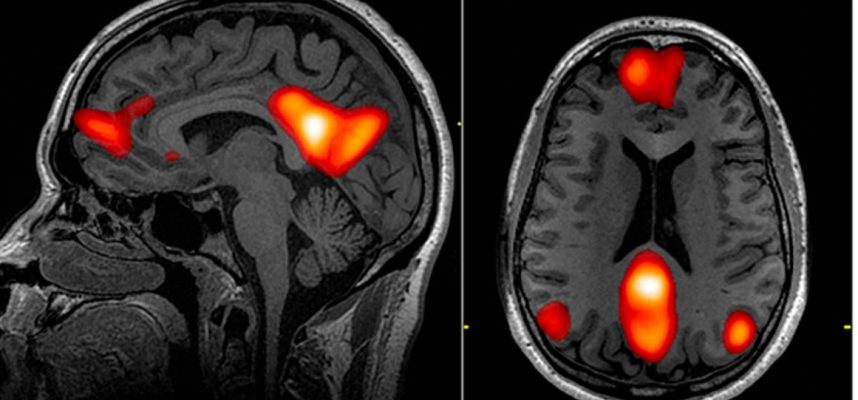

Što se tiče lokaliziranih efekata, trećina svih otkrivenih abnormalnosti pronađena je u frontalnom režnju, dijelu mozga koji obavlja izvršne zadatke razmišljanja, poput zaključivanja i donošenja odluka. Čeoni režanj nam također pomaže u regulaciji osjećaja, kontroliranju ponašanja i uključen je u učenje i pažnju.

“Ovi nam podaci govore da moramo isprobati EEG na širem krugu pacijenata, kao i druge vrste snimanja mozga, poput MRI ili CT, što će nam omogućiti da pažljivije pogledamo frontalni režanj”, rekao je neurolog i koautor studije Zulfi Hanif. sa Medicinskog fakulteta Baylor u Houstonu.